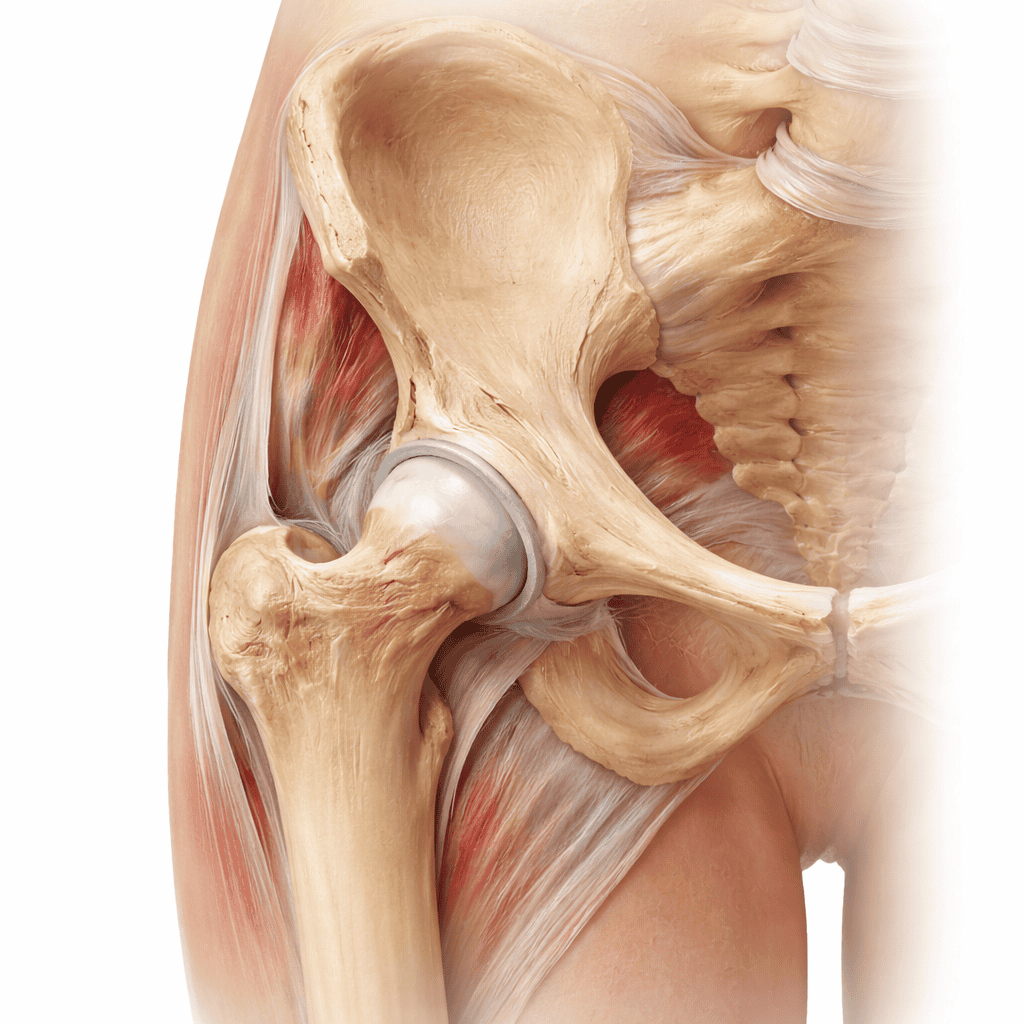

Șoldul este o enartoză — capul femural sferic se articulează cu cavitatea acetabulară a pelvisului, o articulație profundă, stabilă, care suportă forțe de 3–5 ori greutatea corpului la mers. Cartilajul articular, labrumul acetabular și musculatura periarticulară (abductori, flexori, rotatori) asigură funcția normală. Degradarea oricăreia dintre aceste structuri produce durere inghinală tipică, limitarea mobilității și, în forme avansate, șchiopătat. Tratamentul variază de la infiltrații și kinetoterapie, până la proteza totală de șold — una dintre cele mai de succes intervenții din ortopedie.

Structurile articulației șoldului

Înțelegerea anatomiei șoldului explică de ce anumite afecțiuni apar și cum influențează tratamentul:

- Capul femural — sferic, acoperit de cartilaj hialin; vascularizat prin artera circumflexă femurală medială — vulnerabilă la necroză avasculară

- Acetabulul — cavitate hemisferică a pelvisului; adâncit de labrumul fibrocartilaginous care crește stabilitatea și distribuie presiunile

- Labrumul acetabular — inel fibrocartilaginous; lezat în impingement FAI sau instabilitate; produce durere inghinală și senzație de blocaj

- Cartilajul articular — uzura sa progresivă produce coxartroza; ireversibil odată degradat

- Musculatura abductoare — fesierul mijlociu și mic; slăbiciunea lor produce mersul Trendelenburg și tendinopatia trohanterică

- Bursa trohanterică — localizată lateral, pe marele trohanter; inflamată în sindromul dureros trohantteric